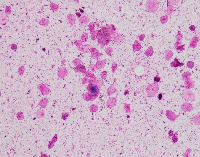

Medical Image Analysis: geckler3 could be used by healthcare professionals, researchers, and medical students to quickly and accurately identify White Blood Cells (WBC) and Erythrocyte-Hemoglobin Concentration (EHC) in clinical images, improving diagnosis and understanding of various blood-related conditions and diseases.

Blood Disorder Diagnosis Support: Implement geckler3 in diagnostic tools to assist doctors in identifying blood disorders, such as anemia or leukemia, by accurately analyzing WBC and EHC levels in blood images, helping with faster and precise diagnosis and treatment.

Biomedical Research: Utilize geckler3 in research laboratories for various biomedical and biotechnological studies to analyze large datasets of blood images, streamlining the process of data collection and analysis by automatically detecting WBC and EHC patterns.

Training and Educational Tool: Integrate geckler3 into educational platforms or applications to help medical and laboratory professionals, as well as medical students, learn and practice the identification of WBC and EHC in blood images, enhancing their skills and knowledge.

Remote Diagnosis Assistance: Employ geckler3 in telemedicine applications, allowing healthcare professionals to remotely access and analyze blood images for the presence of WBC and EHC, aiding in the diagnosis and management of blood-related conditions in areas with limited medical facilities.